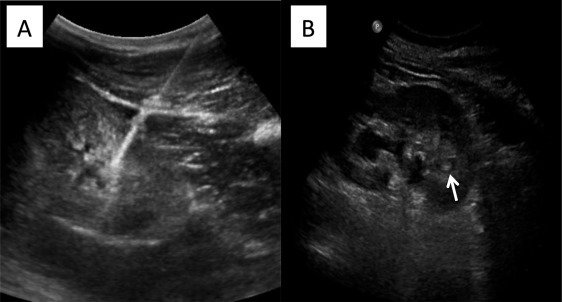

Biopsy

Indication

Preparation for Kidney Biopsy